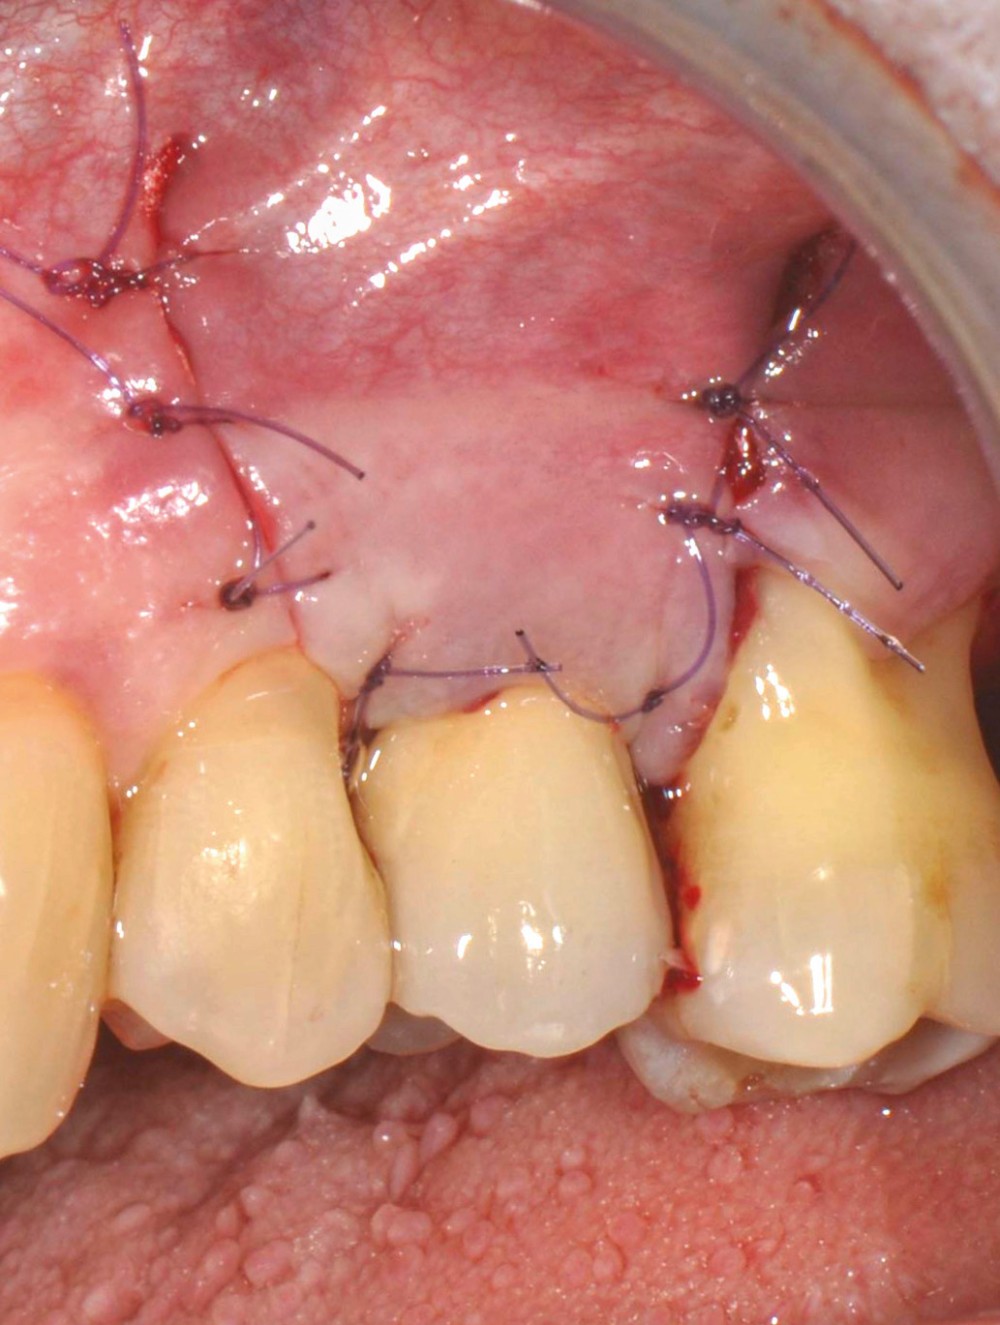

13 et 14. À 3 ans, une régénération osseuse satisfaisante et un bel aspect des tissus péri-implantaires sont observés. Les poches font 3 mm en mésial, distal et palatin, et 2 mm en vestibulaire. Il n’y a pas de saignement au sondage.